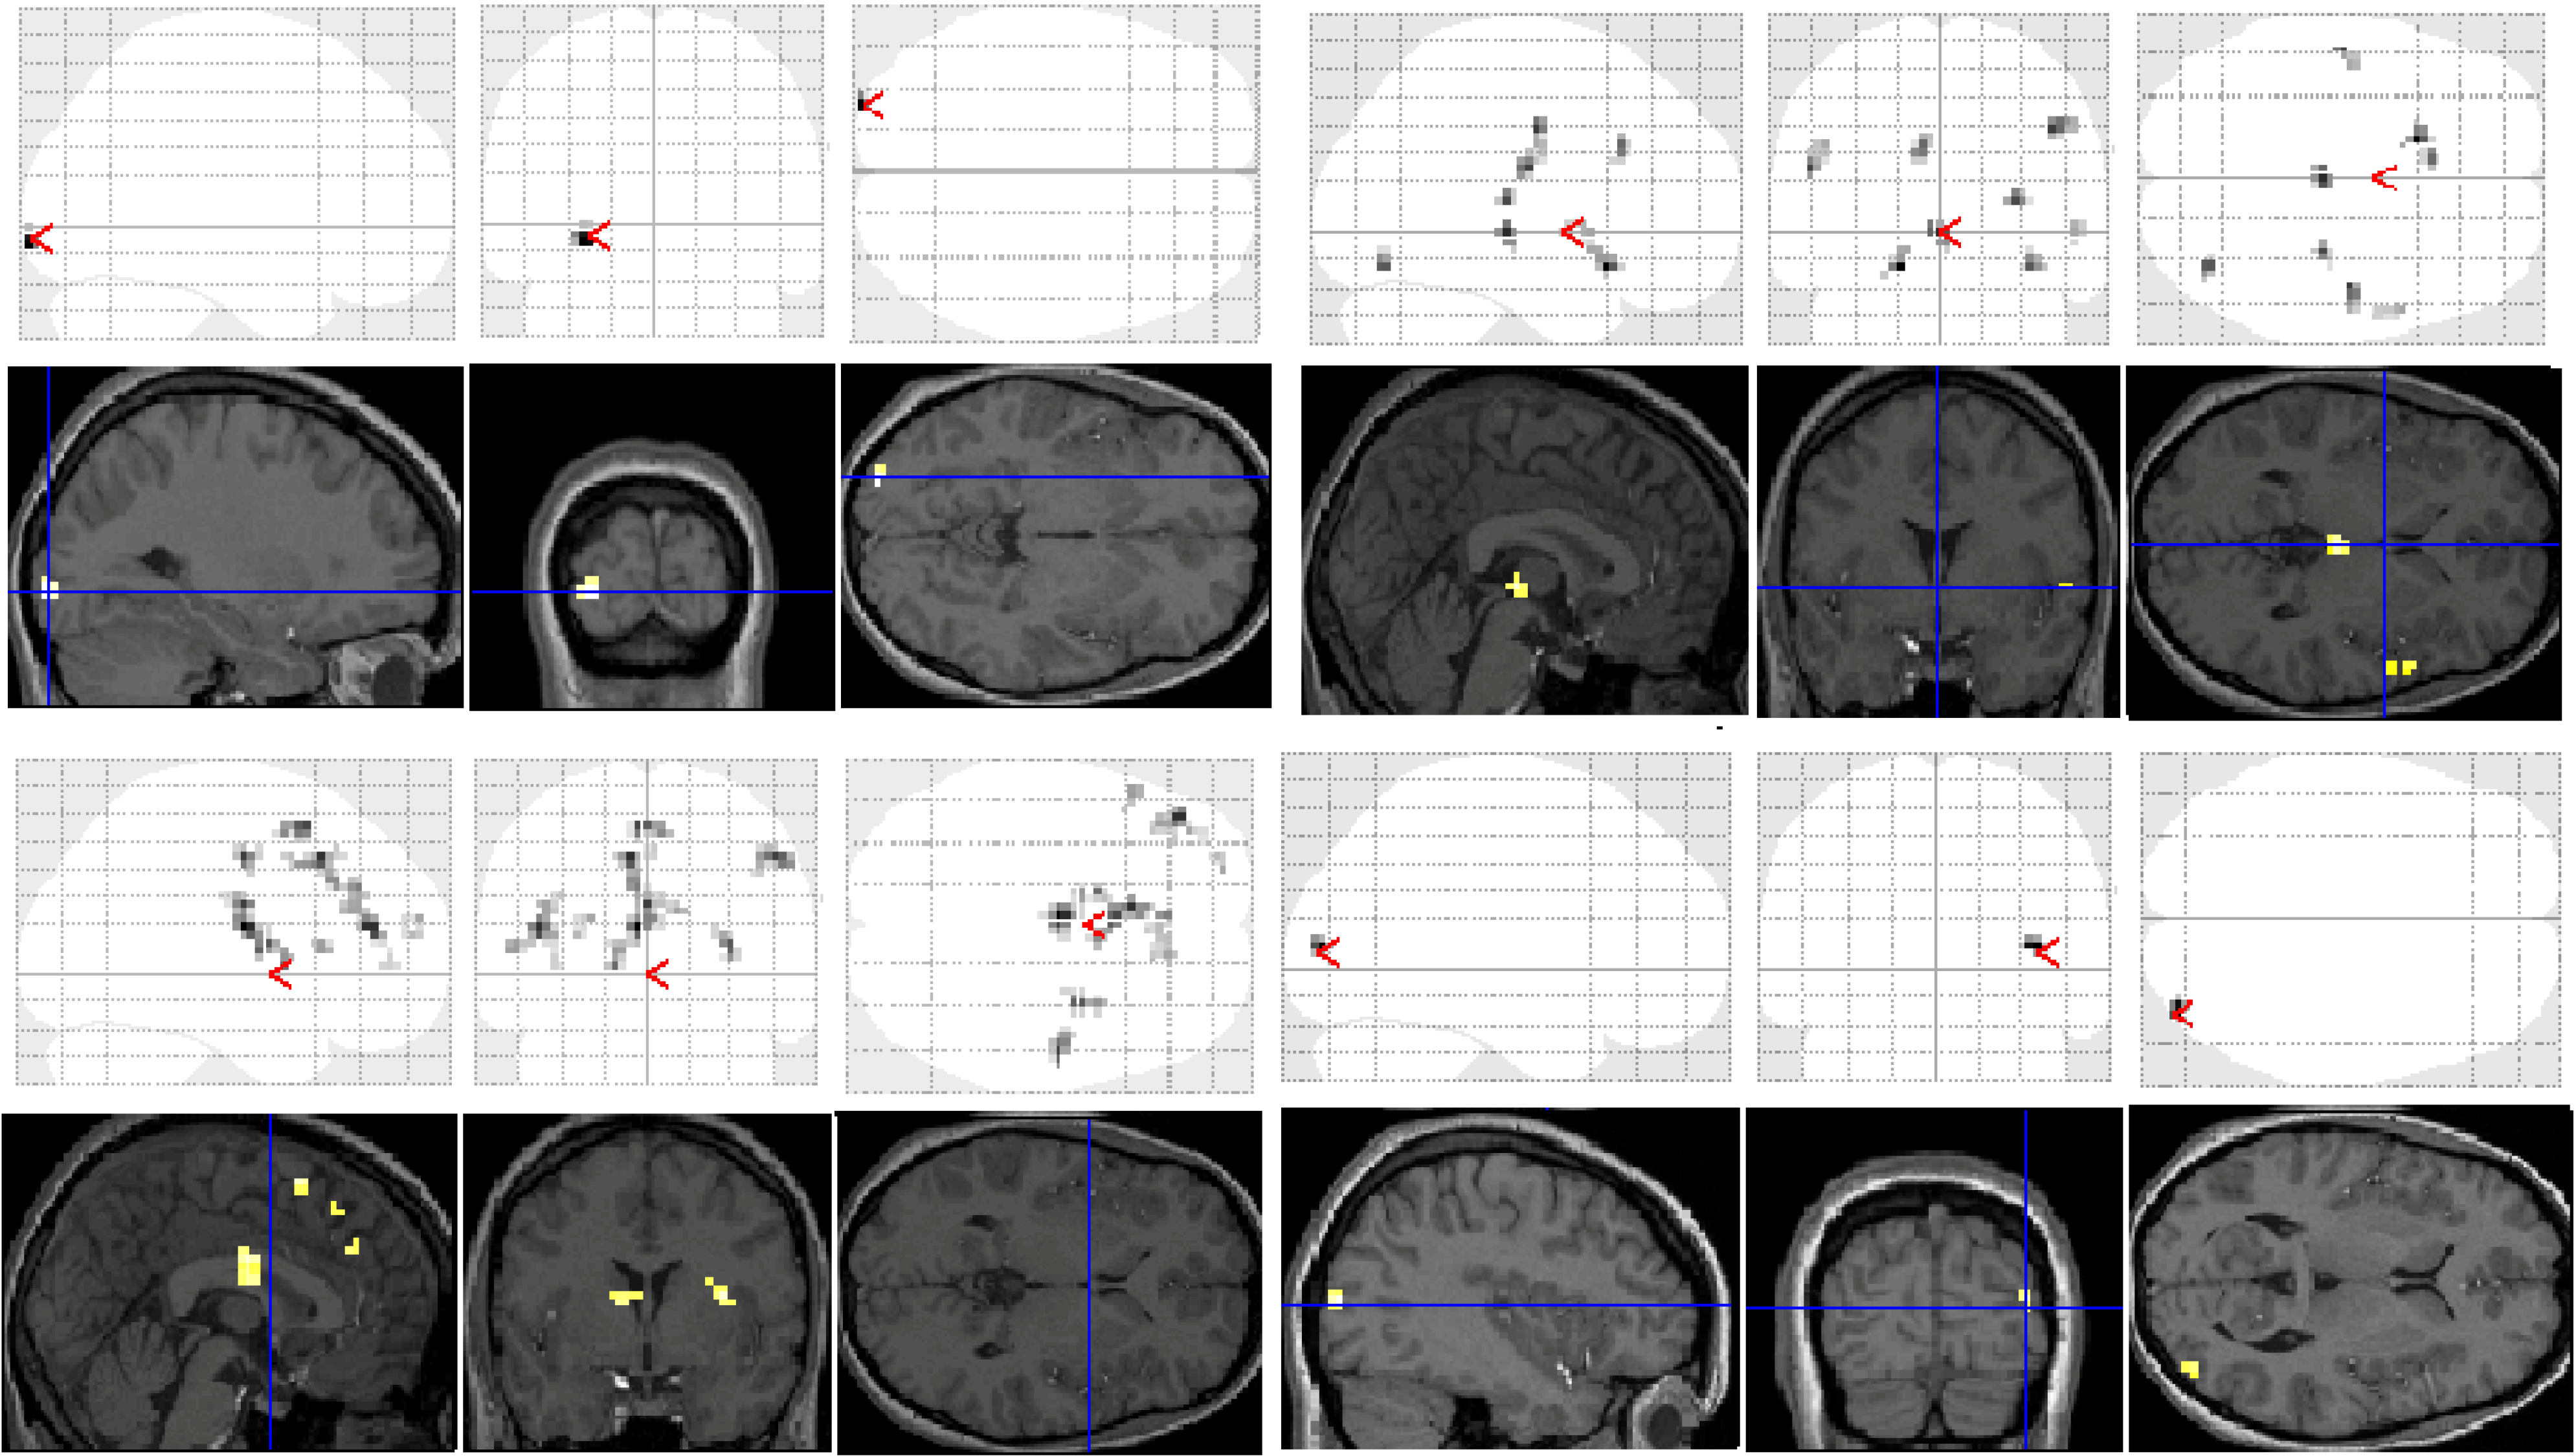

Figure 2. Significant clusters of activation displayed on section overlay and glass brain SPMs observed in participants with dyslexia for each task contrast (versus baseline fixation): letter case judgment (top left); regular word decision (top right); irregular word decision (bottom left); pseudoword decision (bottom right).

Significant group differences in brain activation for each of the contrasts are presented in Table 1 and illustrated in Figure 3. There were no significant differences for the letter case judgment and irregular word tasks.

Significant group differences were observed in the regular word comparison, with typical readers showing greater activation than the dyslexic group in the left inferior occipital gyrus. Dyslexic participants showed greater activation than controls in the left pallidum, the middle cingulate cortex, the cingulate and superior medial gyri, and the middle and superior frontal gyri than non-impaired readers. Dyslexic participants also showed significantly greater activation in the right putamen and precentral gyrus compared with non-impaired readers.

For the pseudoword decision comparison, the analysis revealed significant group differences in both right and left hemisphere activity. In the left hemisphere, dyslexic participants showed greater activation in the putamen, the middle cingulate cortex and the rectal and postcentral gyri than non-impaired readers. In the right hemisphere, dyslexic participants showed lower activation in the right middle occipital gyrus than non-impaired readers but greater activation in the precentral and inferior occipital gyrus, the insula lobe, and the rolandic operculum.

Figure 3. Significant differences between groups for each task contrast displayed on section overlay and glass brain SPMs: regular word decision: Controls > Dyslexics (top left); regular word decision: Dyslexics > Controls (bottom left); pseudoword decision: Dyslexics > Controls (top right); pseudoword decision: Controls > Dyslexics (bottom right).